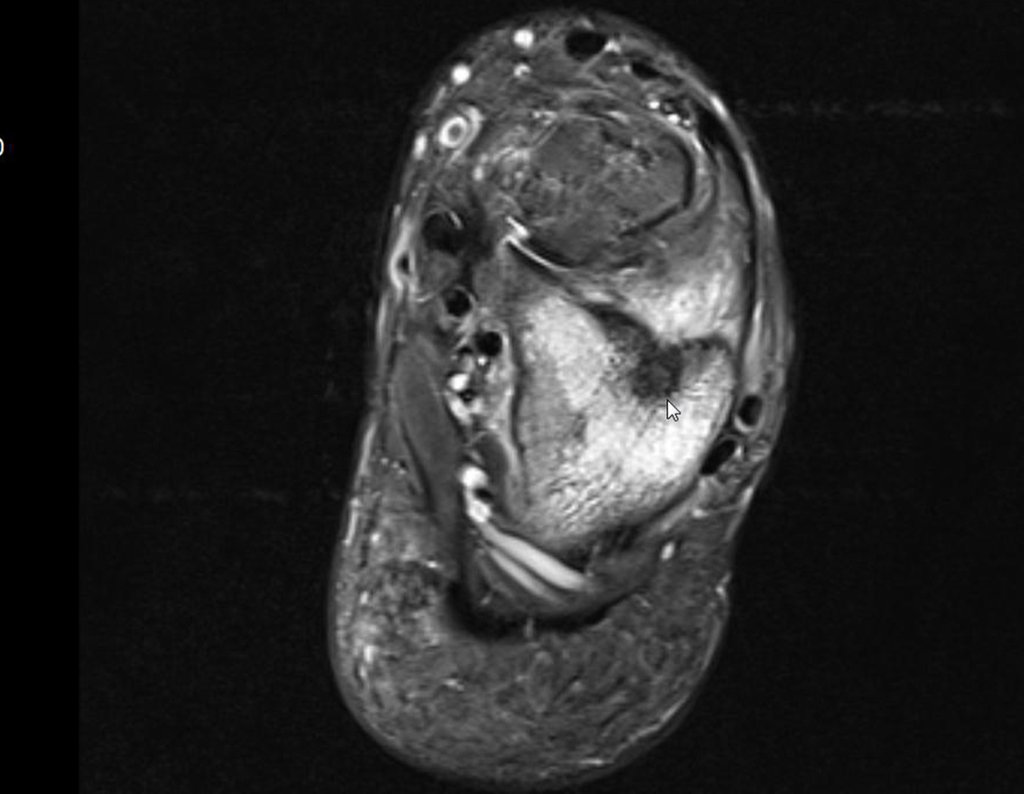

Se indica fisioterapia analgésica y cambio de medicación. Al no mejorar los síntomas, se realizó una resonancia magnética para evaluar mejor el estado.

La paciente es remitida para segunda opinión, siendo evaluada en diciembre de 2014, figuras 35 a 39.